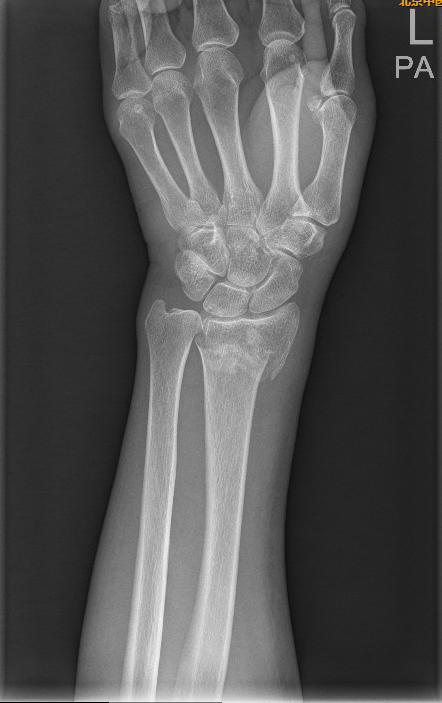

左手桡骨远端骨折图

正常左手桡骨远端图片

桡骨远端骨折